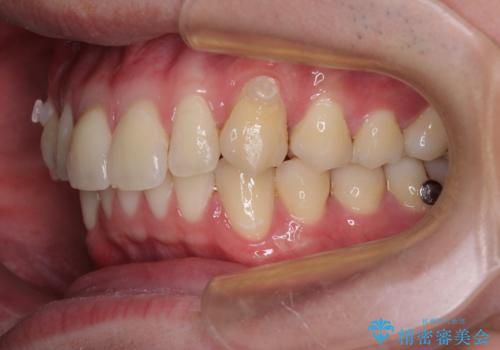

上下のデコボコを治したい インビザラインによる矯正治療

- 前歯のデコボコと突出感を気にして来院された患者様です。

極力目立たない装置を希望とのことで、インビザラインを用いて非抜歯で矯正治療を行うこととしました。

事前に親知らず4本を抜歯し、多少歯列を後方に移動できるように準備をした上で、なるべく歯と歯の間を削ることなくデコボコを解消できるように計画しました。

途中、以前大きなむし歯で処置をした歯が痛み出し、根管治療が必要となったため、根管治療とオールセラミッククラウンによる補綴治療を行い、その後にインビザラインによる仕上げの歯列移動を行い、無事に治療を終えることができました。